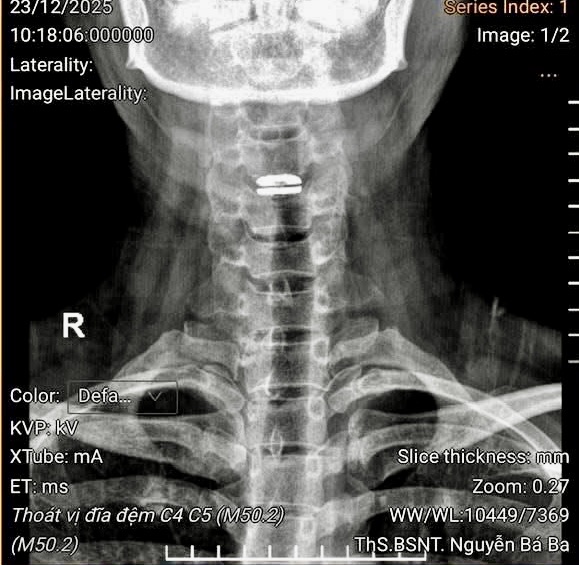

ẢNH: BỆNH VIỆN CUNG CẤP

Qua khám và các hình ảnh chụp chẩn đoán tại Bệnh viện đại học Y dược, bệnh nhân được bác sĩ chuyên khoa phẫu thuật cột sống chẩn đoán bị thoát vị đĩa đệm cổ, chèn tủy sống, nguy cơ bị liệt rất cao, nếu không điều trị, chỉ định phẫu thuật.